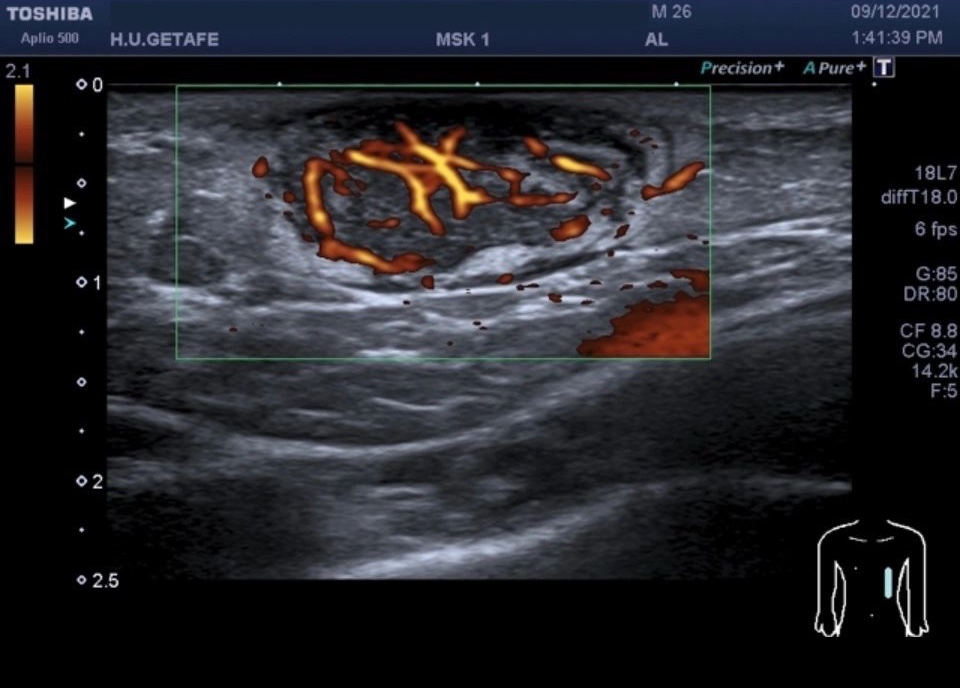

c. Doppler Poder o Power Angio: Muestra la potencia de los ecos de ultrasonido reflejados por el flujo sanguíneo. Proporciona información sobre la presencia e intensidad de los flujos sanguíneos, aunque no muestra velocidades precisas.